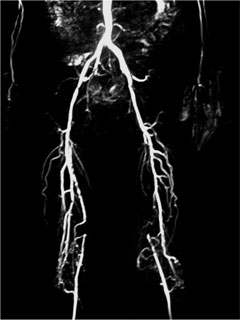

症例8 MRA

Bilateral CIA Stenting (Kissing stent with Palmaz stent)

ABI:右1.0 左0.6